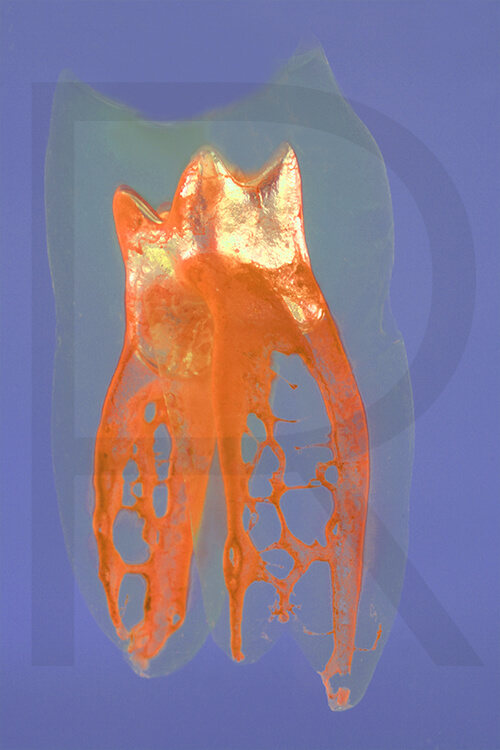

Bildauswahl für Kunstliebhaber

- Foto hinter 3mm Acrylglas, rahmenlos

- hochwertige, unsichtbare Aufhängung, "schwebend“

- Hoher UV-Schutz für lang anhaltend strahlende Farben

- Bruchsicher und leichter als Glas

- Beeindruckende Farben und brilliante Tiefenwirkung

- Druck erfolgt ohne Wasserzeichen

- Bildgröße: 60 x 90 cm, Querformat

Preis: 490,00 Eurozuzüglich 16,90 Euro Versand & Porto innerhalb Deutschlands, weiterer Versand auf Anfrage

Wenn Sie Interesse an den Fotos transparenter Zahnpräparate haben, bieten wir hier die Möglichkeit einige Versionen als Acrylbilder (alle Detailinformationen zu Größe und Preis siehe obige Auswahl) zu bestellen.

Die Bilder sind nicht nur zur Praxisverschönerung geeignet sondern auch eine wertvolle Unterstützung bei der Patientenberatung vor endodontischen Behandlungen.